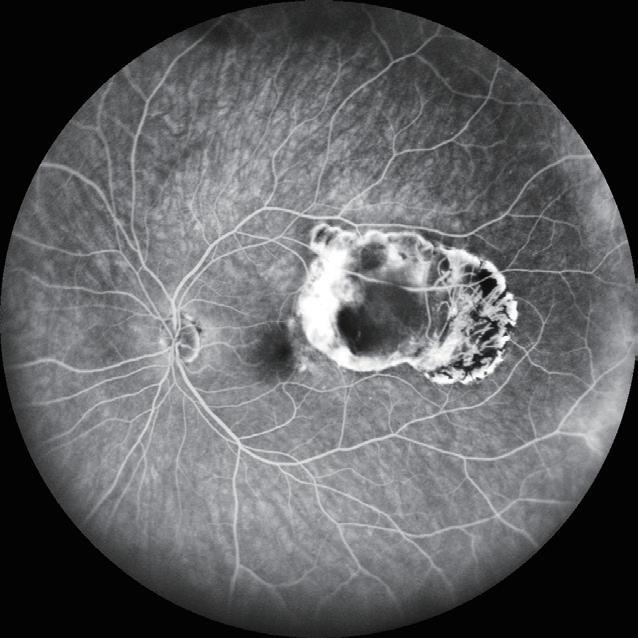

28 Gene Therapy for X-Linked Retinitis Pigmentosa

Robert MacLaren MD, PhD